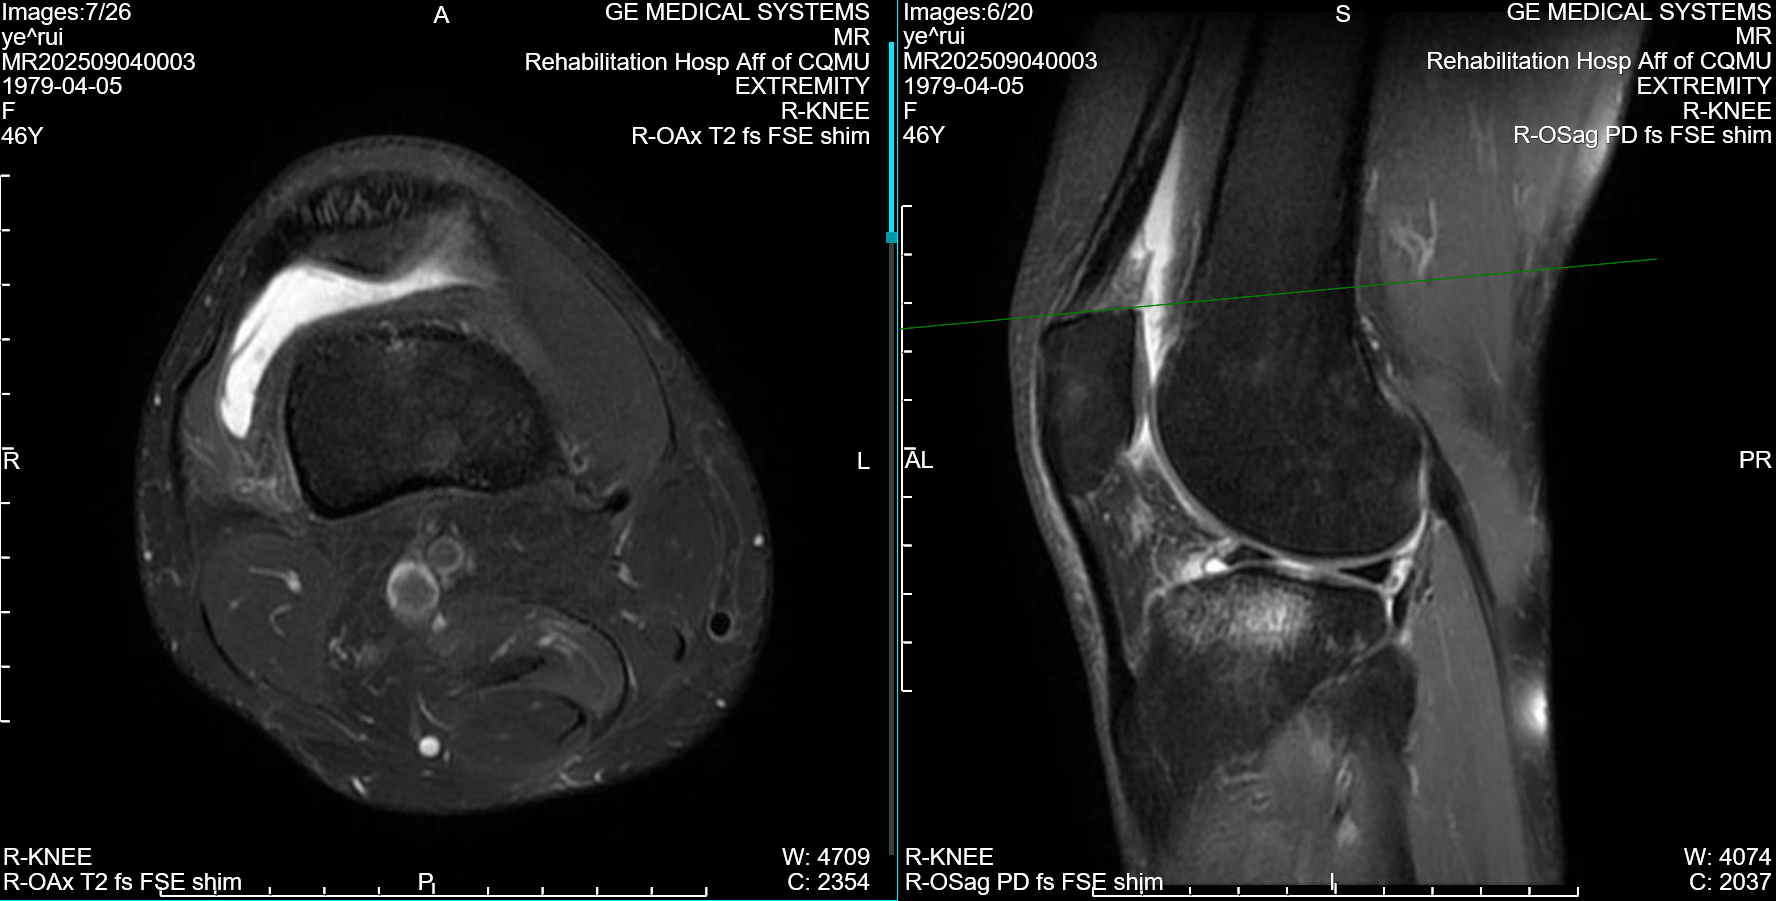

骨折后不到三个月,能否站上全马赛道?近日,马拉松业余跑者叶瑞用实际行动给出了答案。两个月前,她左侧第二趾骨骨折,右侧膝关节还伴有滑膜炎肿胀,在重庆医科大学附属康复医院的科学康复训练下,仅用不到三个月的时间,便顺利重返全马赛场,在湖北来凤马拉松中夺得女子组铜牌,凭借自身毅力与科学康复,实现了重返赛场的心愿。

作为一名马拉松业余跑者,叶瑞在日常训练过程中不慎左趾骨和右膝关节相继受伤。左侧第二趾骨骨折未愈,右侧膝关节又出现严重滑膜炎,肿胀与疼痛让她不得不暂时告别热爱的跑道。1月26日,叶瑞来到重庆医科大学附属康复医院综合康复科接受系统康复治疗及运动训练。针对复杂伤情,医院迅速组建由科室主任陈艳华博士领衔,主管医生欧阳俊琳、治疗师长王晶晶组成专项团队,量身定制分阶段、个体化、闭环式康复方案:康复初期,以消炎镇痛和物理因子治疗控制滑膜炎,缓解疼痛和肿胀;中期逐步引入下肢力量训练、平衡训练,打牢身体基础;后期结合步态分析,纠正跑步姿势,帮助叶瑞逐步恢复跑步能力,确保重返赛场的安全性。康复治疗师王晶晶全程负责具体治疗与训练指导,叶瑞也严格遵从康复计划,咬牙坚持、从不懈怠,全力配合每一项治疗与训练。

经过近三个月的系统科学康复,叶瑞的左侧趾骨骨折愈合良好,右侧膝关节滑膜炎症状缓解,关节功能恢复达到预期。得知叶瑞计划参加湖北来凤马拉松后,综合康复科团队特意为她提供了赛前指导,反复叮嘱她作为骨折康复后的首个全马赛事,务必量力而行,以完赛为首要目标,切勿急于求成、盲目激进,叶瑞将这份叮嘱牢记于心。